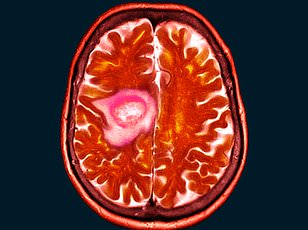

Ms. Whittaker, a health and hygiene worker, was referred to an eye clinic after her optician flagged persistent visual disturbances. There, imaging revealed a tumor pressing against her optic nerve, causing her left eye to bulge and threatening her vision. Her neurologist's questions about her medical history took an unexpected turn when he inquired whether she had ever used the contraceptive injection medroxyprogesterone, marketed as Depo-Provera. Ms. Whittaker confirmed that she had been prescribed the jab for 15 years—a revelation that prompted the doctor to urge her to stop immediately, citing its potential links to meningiomas.

The surgery to remove 90% of the tumor was a grueling 10-hour procedure, leaving Ms. Whittaker with a permanent reminder of the risks she had unknowingly taken for over a decade. "I used to encourage people to take it, like me," she said, reflecting on her past advocacy for the contraceptive. "It needs to be out there that there are risks if you're a long-term user of it." The remaining 10% of the tumor could not be safely removed due to its proximity to her optic nerve, leaving her with a lifelong condition that requires ongoing monitoring.